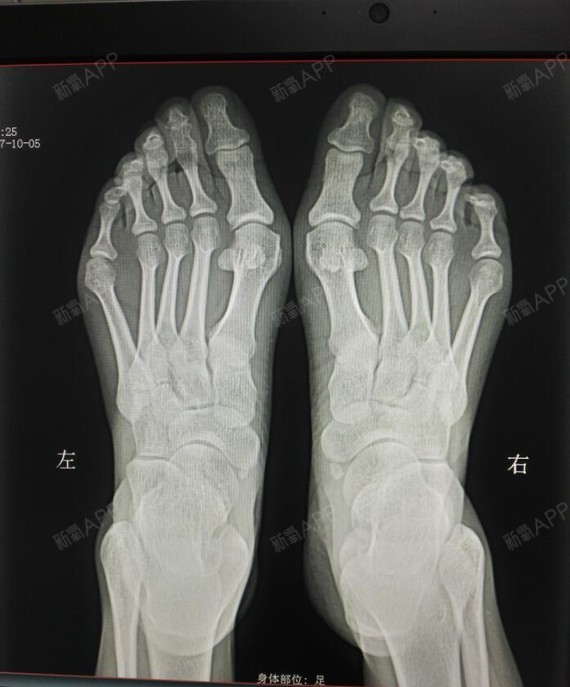

x光片更直观了解大脚骨 如果单纯去掉凸起能否有效矫正拇外翻呢?

我脚的问题有点多,不仅有大脚骨,还有脚趾畸形,小脚_圈子-新氧美容